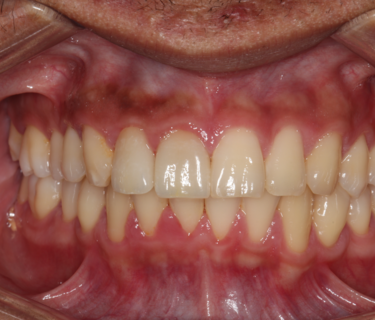

At the final appointment her comment that the temporaries were too white and didn’t match the rest of her teeth was noted for milling of the final restorations (Figures 12-13).  The final restorations were milled and seated in the mouth at that second visit (Figure 14).

Figures 12: The final milled restorations on the model and seated in the mouth.

Figures 13: The final milled restorations on the model and seated in the mouth.